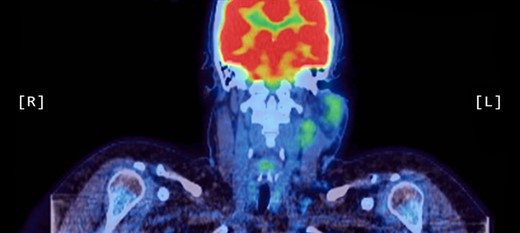

A computed tomography (CT) scan demonstrated left parotid multifocal soft tissue abnormality and enlarged left-sided cervical lymph nodes, with prominent superficial left supraclavicular fossa lymph nodes (Figs 3 and 4).

Axial CT sinuses (with contrast) showing left parotid multifocal soft tissue abnormality and enlarged left-sided cervical lymph nodes.